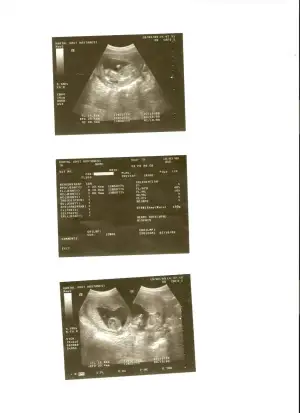

Kimler kimler yazdı?canim yaa bence o bebisin eli.kol kemigini takip et bak bi..hayirlisi olsun insallah.bana eliymis gibi geldi.CADIARZUcünkü o kadar büyük olmuyo benimde oglum olcak hayirlisiyla ordan biliyorum azicik yani.

canım kolla karışmasın diye işaretleyip ikinci kez gene yolladım altlarda ok

teşekürler kızlar hepiniz sağolun...bunuda başka bir hastanede çekilmiştim.hatta doktor 14 cm 133 gr diyince afallamıştım..çünkü bebek daha 13+3 tü...çok merak ediyorum bu cuma kendi doktorum ne dicekk:)

cnm 14cm ayaklarına kadar olan boyudur onun.benım doktorum FL uzunlugunu 7 ıle carparak da hesaplıoruz demıstı boyunu.senın FL=10.8 onu 7 ıle carpınca 12.6cm oluo o da normal zaten.

canım kolla karışmasın diye işaretleyip ikinci kez gene yolladım altlarda ok

evet canim sonradan gördüm onu.hayirlisi olsun insallah erkek olabilir.bakalim gelecek randevunda ne diycek dr.un.saglikli olsunda hayirlisiyla.ama erkekler erkenden gösteriyolarmis yukarida oldugu icin pipileri.kizlarin assada oluyo ya.erkek olmasi büyük olasilik yani.hayirlisi allahtan..